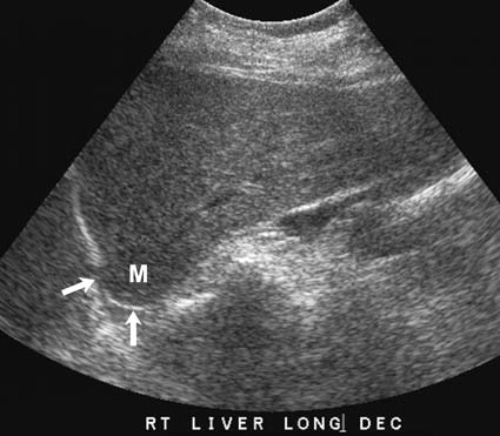

Артефакт скорости звука обусловлен прохождением звуковой волны через какое-либо вещество со скоростью, которая значительно отличается от нормальной – 1540 метров в секунду (см статью «Основы УЗИ»). То есть, если какая-либо ткань замедляет скорость звука, проходящее сквозь нее эхо задерживается, в результате чего глубина объекта определяется большей, чем есть на самом деле (рисунок 9).

Рисунок 9. УЗИ печени: Артефакт скорости звука. Стрелками отмечена диафрагма, на которой наблюдается почти изоэхогенное образование (М), локализованное кпереди от диафрагмы. Учитывая тот факт, что через данное образование волны проходят медленнее, эху нужно больше времени, чтобы вернуться от диафрагмы к датчику, чем при прохождении ткани здоровой печени. Таким образом, на изображении отмечается изменение ткани печени